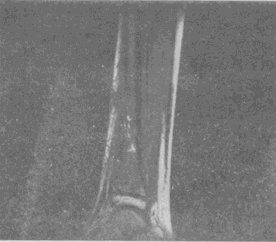

男,33岁,有发热,小腿局部有疼痛,红肿并有压痛,结合图像,最可能的诊断是

男,33岁,有发热,小腿局部有疼痛,红肿并有压痛,结合图像,最可能的诊断是<img border="0" style="width: 324px; height:

[单选题]男,33岁,有发热,小腿局部有疼痛,红肿并有压痛,结合图像,最可能的诊断是A.骨髓炎B.脂肪瘤C.未见异常D.骨髓瘤E.骨化性肌炎

男,33岁,有发热,小腿局部有疼痛,红肿并有压痛,结合图像,最可能的诊断是

[单选题]男,33岁,有发热,小腿局部有疼痛,红肿并有压痛,结合图像,最可能的诊断是A.骨髓炎B.脂肪瘤C.未见异常D.骨髓瘤E.骨化性肌炎

男,33岁,有发热,小腿局部有疼痛,红肿并有压痛,结合图像,最可能的诊断是()

[单选题]男,33岁,有发热,小腿局部有疼痛,红肿并有压痛,结合图像,最可能的诊断是()A . 骨髓炎B . 脂肪瘤C . 未见异常D . 骨髓瘤E . 骨化性肌炎

男,33岁,有发热,小腿局部有疼痛,红肿并有压痛,结合图像,最可能的诊断是()

[单选题]男,33岁,有发热,小腿局部有疼痛,红肿并有压痛,结合图像,最可能的诊断是()A .骨髓炎B .脂肪瘤C .未见异常D .骨髓瘤E .骨化性肌炎